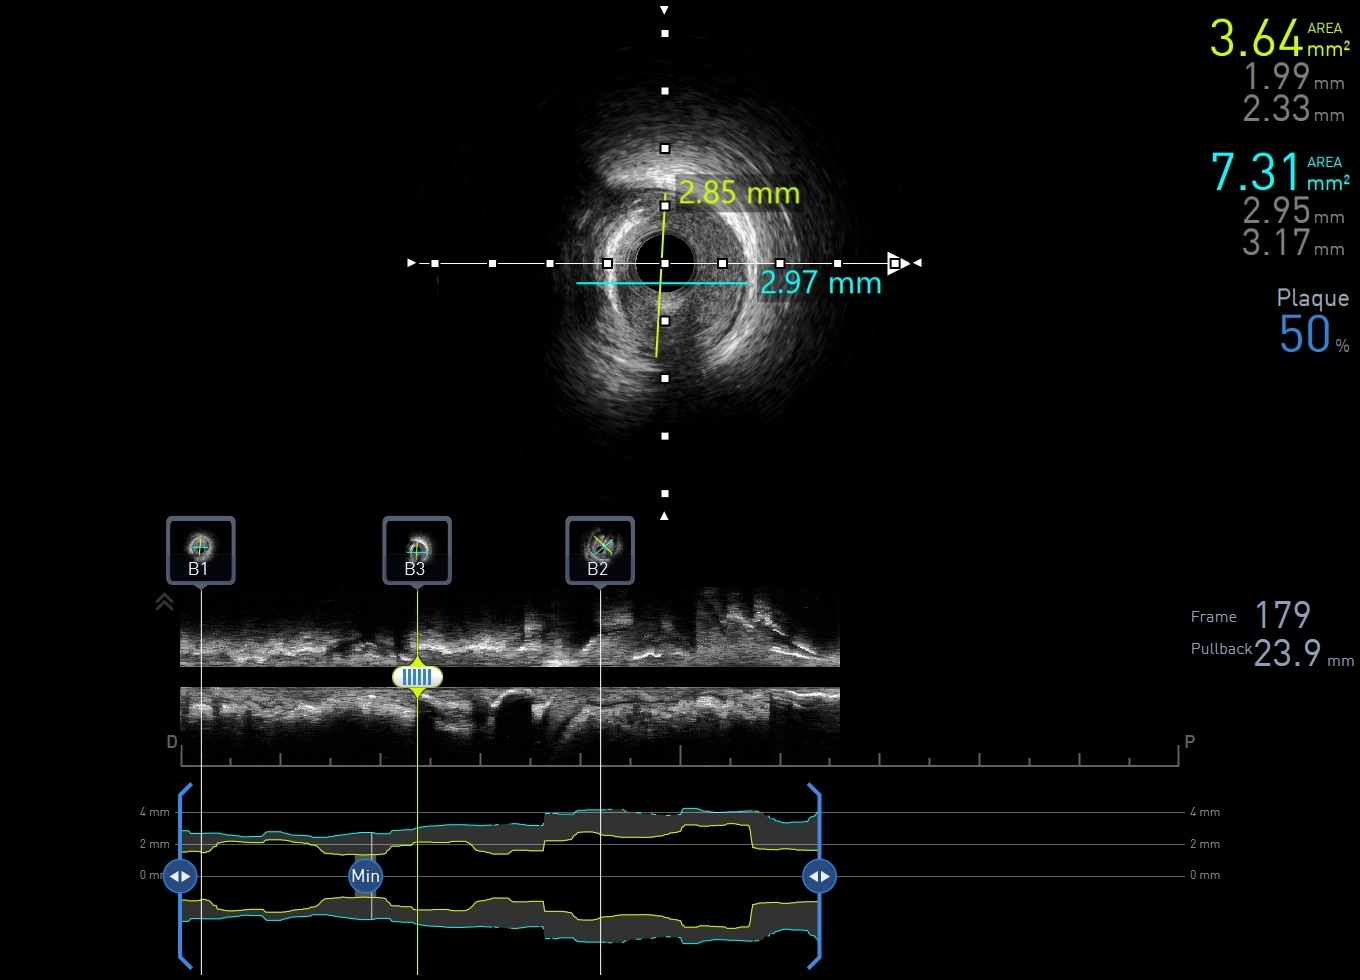

Coronary intervention was performed using an EBU 3.0, 6 Fr guiding catheter via the right radial artery approach. A Runthrough Floppy wire was advanced to the distal first LAD, and a Sion Blue wire to the second LAD. Pre-dilatation of the mid first LAD was performed using a semi-compliant (SC) 2.0 ¡¿ 15 mm balloon at high pressure. Intravascular ultrasound assessment revealed fibrocalcific plaque in both vessels. The vessel reference diameter of the first LAD measured 2.5 mm distally and 3.0mm proximally, with a minimal lumen area of 5.5–6.0 mm©÷ at the ostial segment. The second LAD had a vessel reference diameter of 2.5 mm distally and 2.75 mm proximally. Pre-dilatation of the second LAD was performed using a SC balloon at nominal pressure. Vessel preparation of the first LAD was then performed using a non-compliant (NC) 2.0 ¡¿ 10 mm balloon, followed by a scoring balloon(2.5 ¡¿ 15 mm) inflated at high pressure. The lesion was adequately prepared with minimal recoil and a type B non–flow-limiting dissection observed indicating adequate vessel preparation before DCB angioplasty. Two drug-coated balloons were inflated in the first and second LAD at nominal pressure for 45 seconds each. Similar non–flow-limiting type B dissections were observed in both LADs, with minimal recoil. Final angiographic results were satisfactory showing TIMI 3 flow with no immediate complications. The patient remained asymptomatic and discharged well the following day.